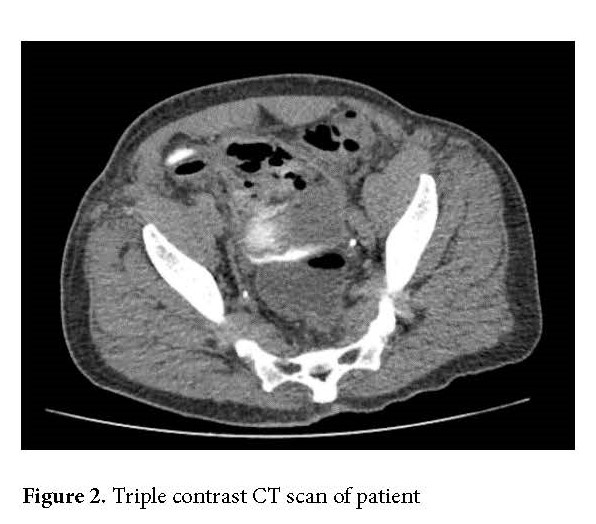

On postoperative day 41, the patient returned to the emergency department with symptoms of fatigue, dysuria, and foul-smelling urine. A CT scan with intravenous, rectal, and oral contrast was performed, raising suspicion for an enterovesical fistula (Fig. 2). The patient was subsequently taken to the operating room for cystoscopy and cystography, which revealed necrosis of the right lateral bladder wall and dome, along with the presence of an extraperitoneal fistula.